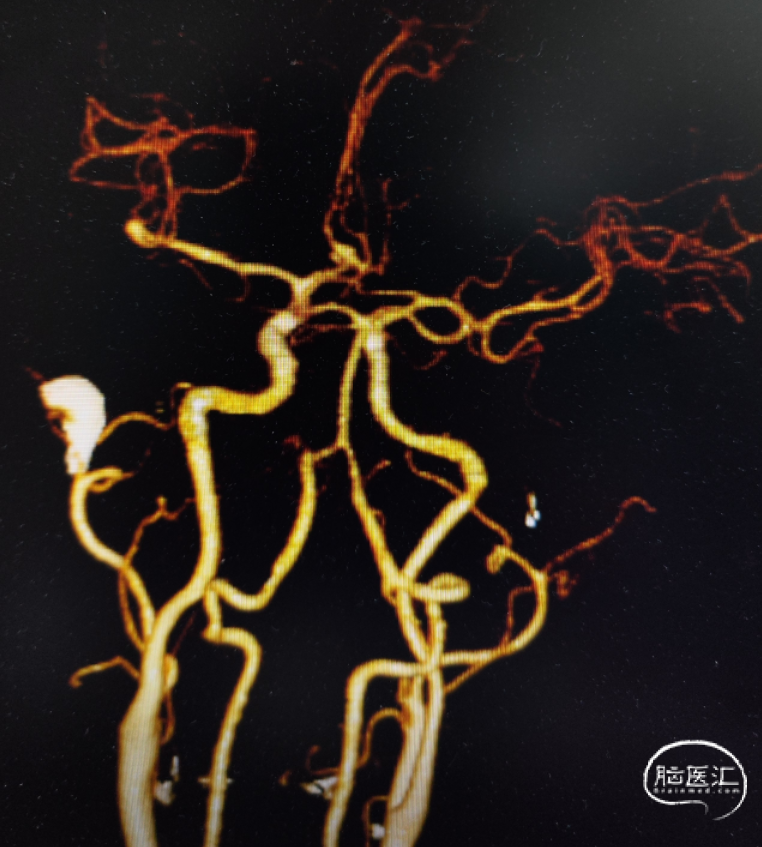

影像信息

完善头颅CTA显示:前交通动脉瘤、左侧大脑中M1段末端动脉瘤。

DSA造影确认前交通动脉瘤、左侧大脑中M1段分叉部动脉瘤。

前交通动脉瘤5.94mm*4.12mm,瘤体呈分叶状。

患者右侧大脑前发育纤细;后循环血管无明显异常。